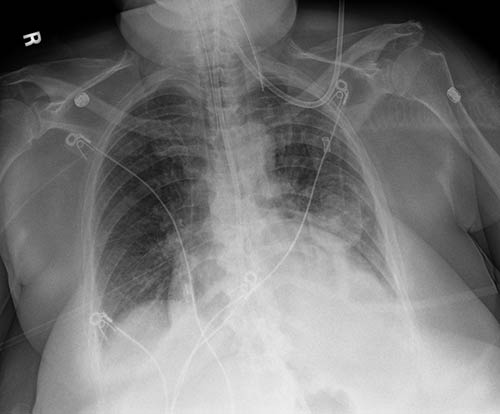

Tenha certeza com uma única exposição. O aprimoramento de tubo e linha cria uma imagem complementar e utiliza processamento otimizado para a visualização mais nítida e simplificada das linhas e dos tubos do PICC. Aumenta a confiança de que os tubos e as linhas estão posicionados corretamente e permanecem no lugar.